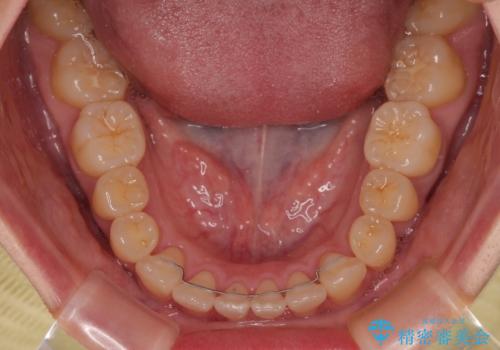

- 上下前歯のデコボコやクロスバイトを気にして来院された患者様です。

上顎歯列が下顎の歯列に対して狭小であり、一部下顎の奥歯が上顎よりも外側に位置している状態でした。

上顎の急速拡大装置を使用して上顎骨を側方に拡大することで上顎歯列を拡大し、下顎歯列も拡大できるようにすることで、歯列を整えることとしました。